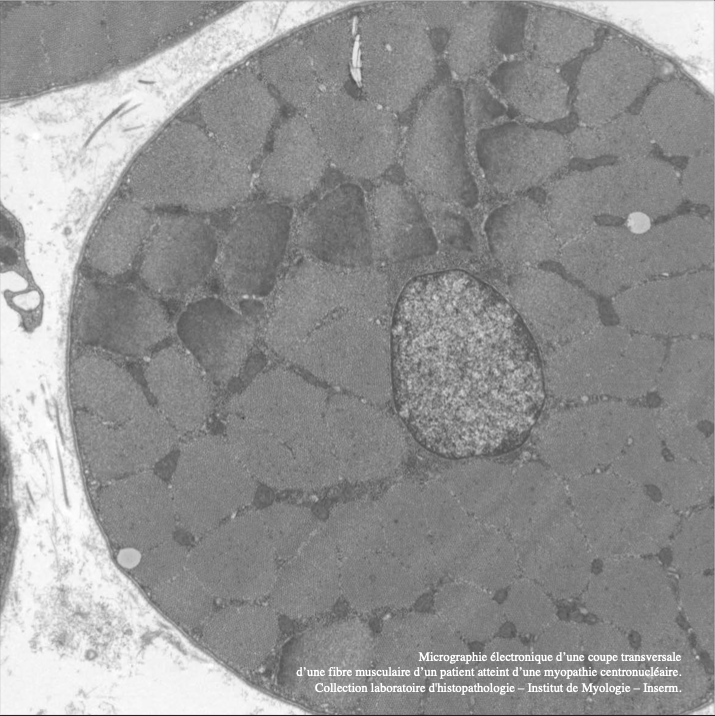

Livre M. Fardeau (N. Bignier, S. Vassilopoulos, A. Rouche) – lame myopathie centronucléaire NB